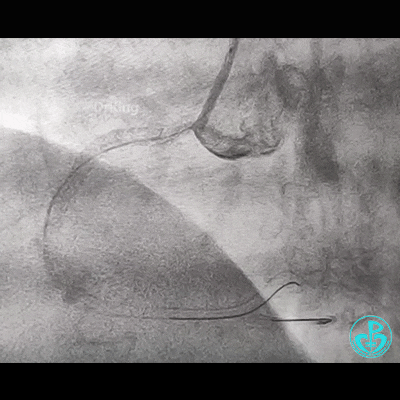

冠脉造影

右锁骨下动脉迂曲打圈,影像如下: